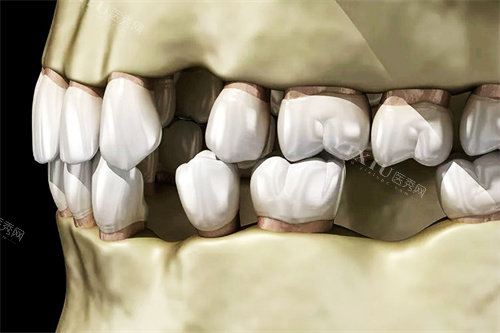

4. 智能化正畸系统

"轻快矫"正畸系统采用智能化技术预先模拟治疗结果,使用靠谱材质,矫正过程快速省时。不仅能有效改善牙齿排列问题,还能调整面容美观度,性价比高。适用于牙齿不齐、拥挤、地包天、龅牙、牙间隙过大及露龈笑等多种情况。